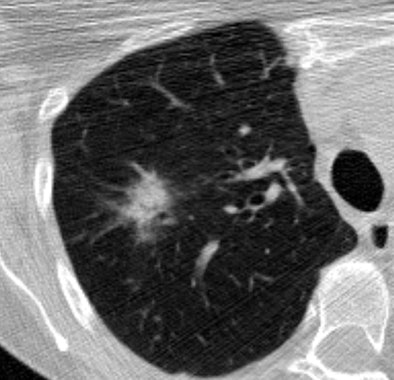

![]() |

| CT image above shows extensive calcification along the carinal ridge of an airway bifurcation. The image is displayed without interpolation so that individual pixels are easily discerned. The peak voxel density along the carinal ridge shown in the slice is 614 HU. The DICOM header reveals that the CT data were acquired at 80mA, 120 kVp, 1.25-mm slice thickness, and with the bone kernel on a LightSpeed Ultra scanner (GE Healthcare, Chalfont St. Giles, U.K.). The bone kernel is not edge-enhancing, so the observed density cannot be due to the kernel; the densities were likely reduced due to partial volume artifact (the 614 HU voxel is adjacent to air). Image below from the same dataset case shows a part-solid lesion in the upper lobe of the right lung. All images courtesy of the Public Lung Database to Assess Drug Response. |